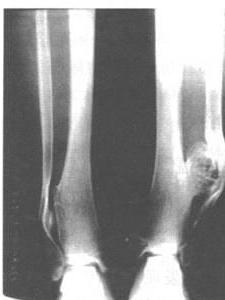

这种病的很大特点在于有成的缺陷和骼畸。特是在髋部可呈双侧髋外翻及股骨近侧端变宽(图3)。腕关节出现逐渐的尺骨偏斜、尺骨相对短缩等。